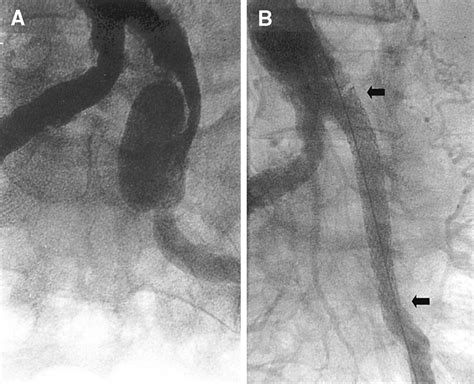

1. Endovascular Repair (EVAR/EVIA)

This is the less invasive approach. A surgeon inserts a catheter through a small incision in the groin. Using specialized imaging, a stent-graft is guided into the iliac artery to reinforce the wall and redirect blood flow away from the weakened area. This technique typically results in faster recovery times.

• iliac artery aneurysm radiology